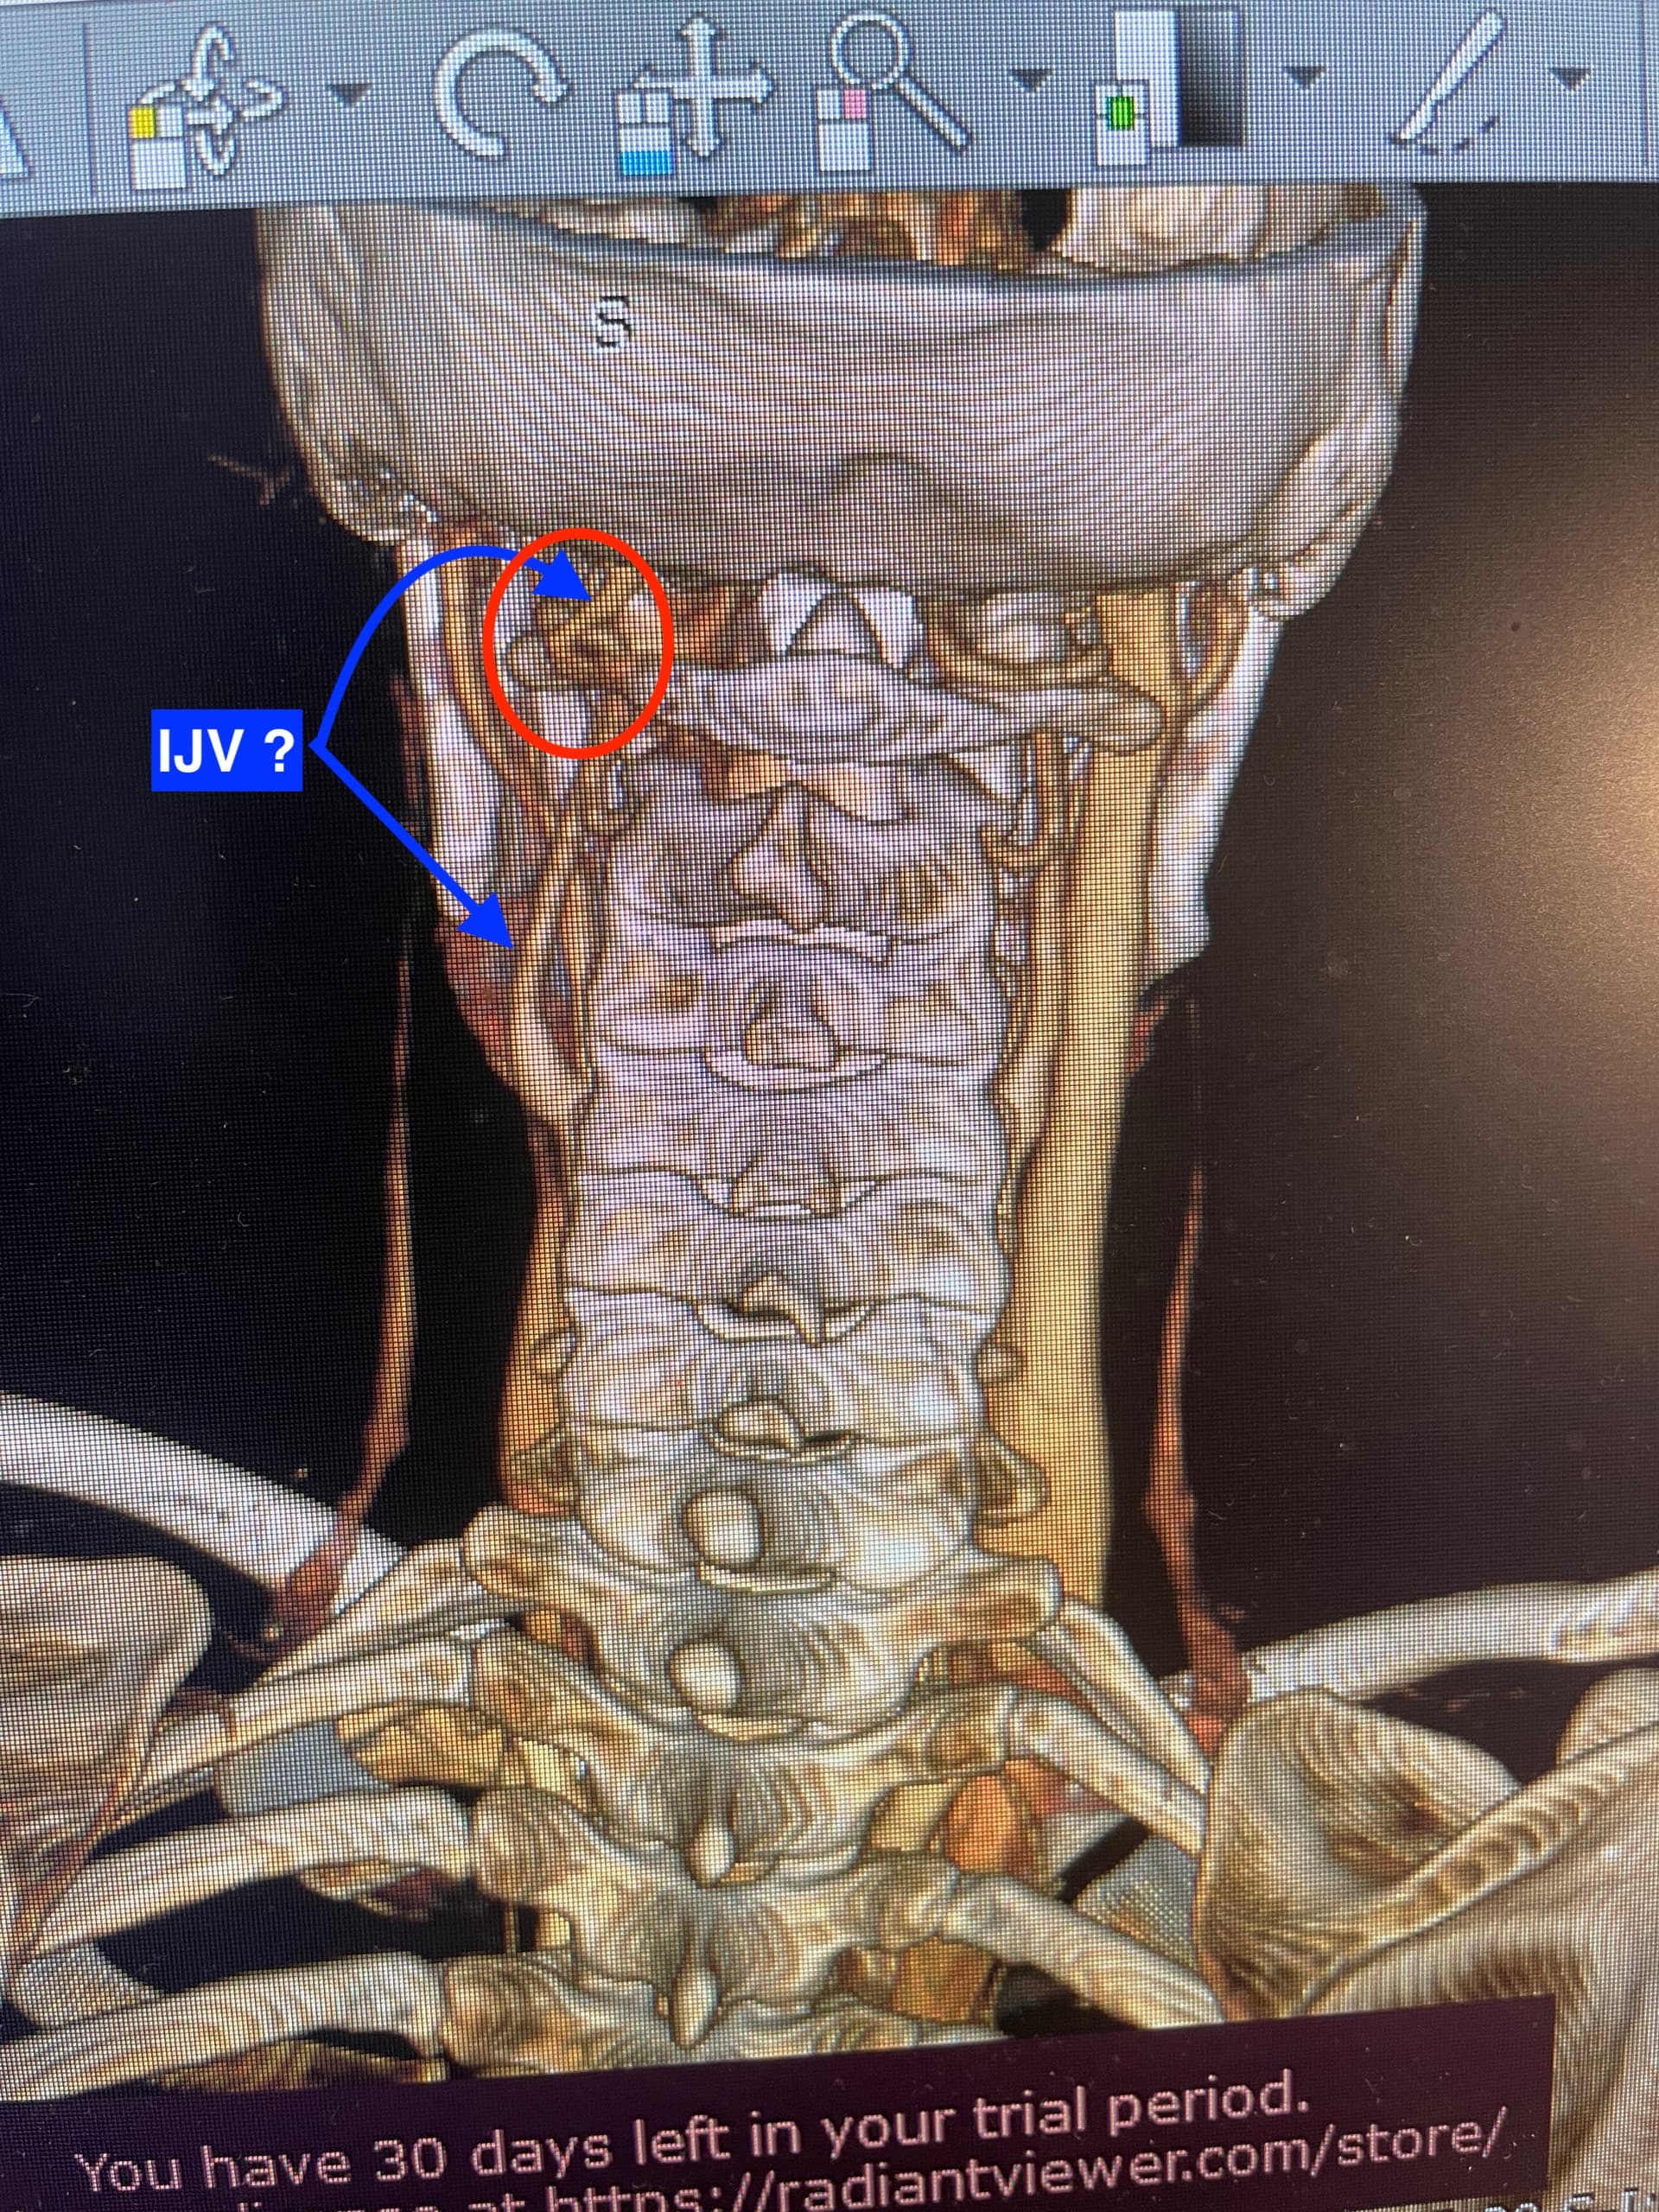

@Coco1 see attached annotated image.

Your left styloid is really close to your C1. This poses a potential issue for your left IJV and left vagus nerve, since typically, the IJV and vagus nerve are between the styloid and C1. However, I don’t see your IJV there. Maybe this is because it doesn’t have contrast in it, or it’s because it’s further out to the side (where I labelled “left IJV?”). Nonetheless, the styloid should not be that snug against C1 because it risks irritating and/or compressing nerves.

On your right side, the styloid seems to be an o.k distance from your IJV. The IJV may have some compression against C1, but not sure if this is enough to cause problems.

I’m just noticing this as I write this, but the white glow in the bottom right of the image that hugs along the bottom of the C1 transverse process appears it could be a collateral vein. We typically develop these in response to IJV compression, so the blood can flow out of the brain. The fact that this is on the same side (i.e., your left side) as the styloid that is abnormally close to your C1, I suspect your left IJV is being compressed.